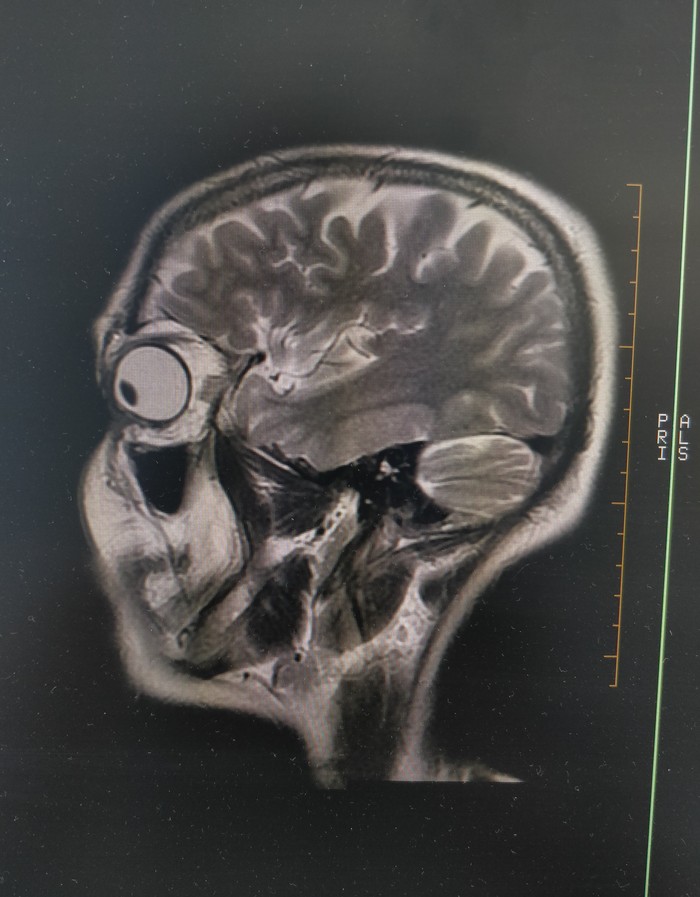

2. Часто получается такая дичь)